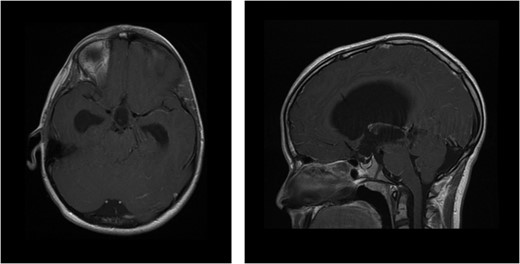

CT scan of the brain showed acute hydrocephalus with massive dilatation of lateral and third ventricles (at mesencephalon and thalamus levels, respectively).

MRI of brain enhanced with contrast agent showing ventricular dilatation with aqueducts occlusion (axial and sagittal sequences, respectively).